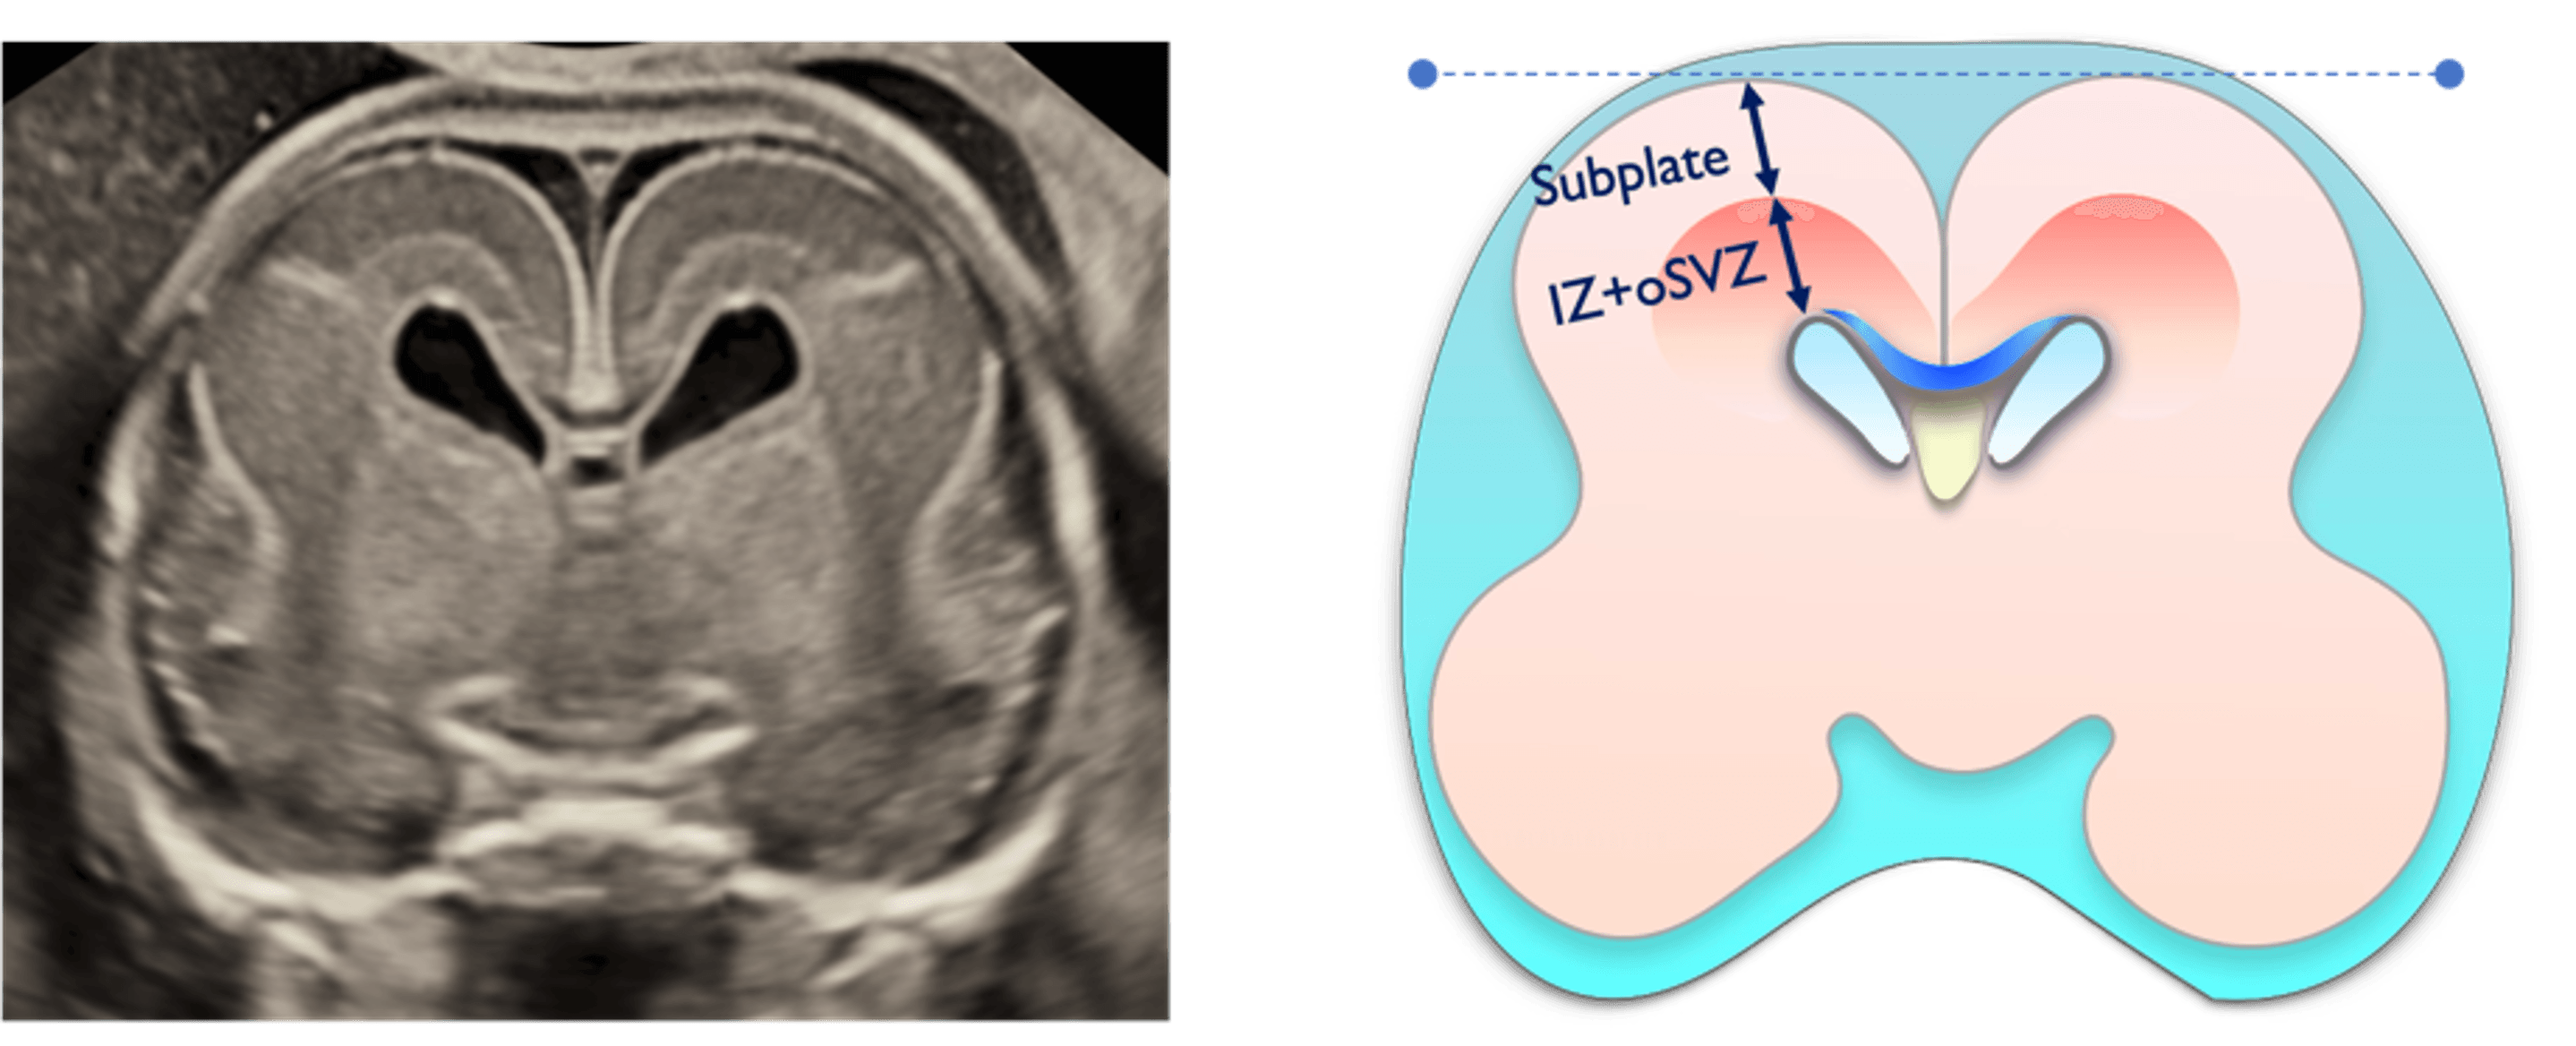

夫 律子院長が発表した研究は、胎児の脳における「サブプレート」と呼ばれる脳層に着目したものです。サブプレートは胎児期の一定の時期にしか観察されることがない特殊な脳層で、ヒトの大脳皮質形成初期においてニューロンの移動や神経回路の形成に重要な役割を果たし、神経発達の鍵を握る構造として注目されています。このサブプレートに着目して実際の胎児での観察実績をもつのは現在のところ世界でもクリフム出生前診断クリニックだけです。※当院調べ

方法:高精度3D経膣脳神経超音波による脳の詳細計測

結果:先天異常を持つ胎児群を複数のグループに分類し、サブプレートの発達パターンを比較分析した結果、グループ間で明確な発達の違いを確認。